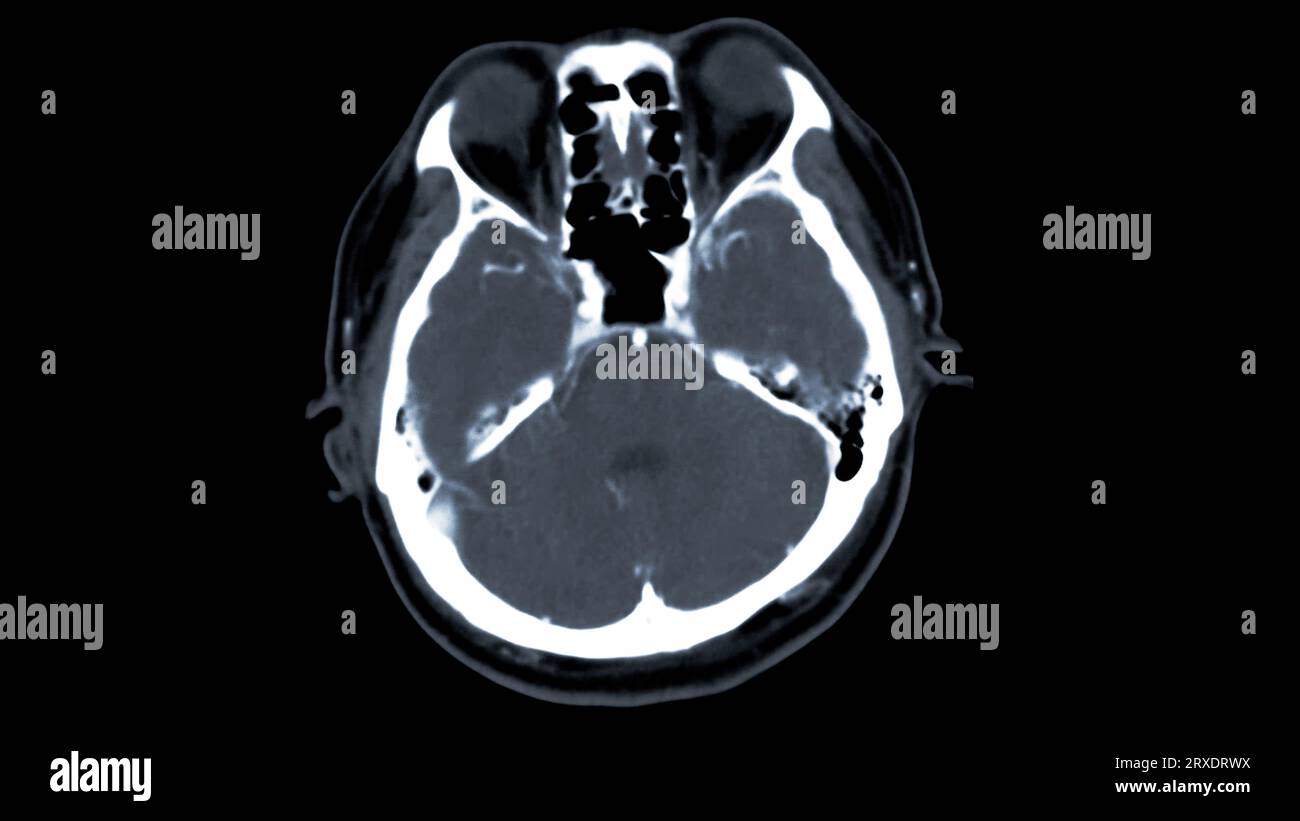

Cas d'accident de moto avec un léger parjure traumatique du cerveau et CT du cerveau montrent une fracture maxillaire droite avec le sang dans le sinus maxillaire Banque D'Imageshttps://www.alamyimages.fr/image-license-details/?v=1https://www.alamyimages.fr/cas-d-accident-de-moto-avec-un-leger-parjure-traumatique-du-cerveau-et-ct-du-cerveau-montrent-une-fracture-maxillaire-droite-avec-le-sang-dans-le-sinus-maxillaire-image472227243.html

Cas d'accident de moto avec un léger parjure traumatique du cerveau et CT du cerveau montrent une fracture maxillaire droite avec le sang dans le sinus maxillaire Banque D'Imageshttps://www.alamyimages.fr/image-license-details/?v=1https://www.alamyimages.fr/cas-d-accident-de-moto-avec-un-leger-parjure-traumatique-du-cerveau-et-ct-du-cerveau-montrent-une-fracture-maxillaire-droite-avec-le-sang-dans-le-sinus-maxillaire-image472227243.htmlRF2JC7PJK–Cas d'accident de moto avec un léger parjure traumatique du cerveau et CT du cerveau montrent une fracture maxillaire droite avec le sang dans le sinus maxillaire